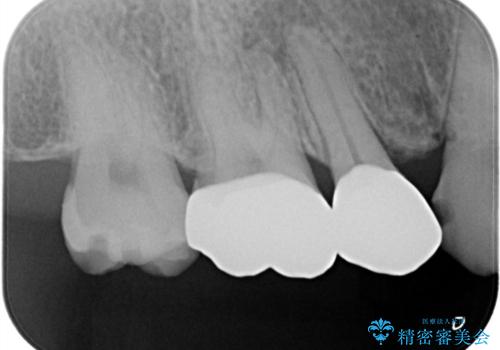

- メタルフリー治療を希望されオールセラミッククラウンにて修復しております。

近遠心の辺縁隆線がなくなっている歯は破折抵抗が著しく低下するため、破折防止のためにクラウンを希望されました。